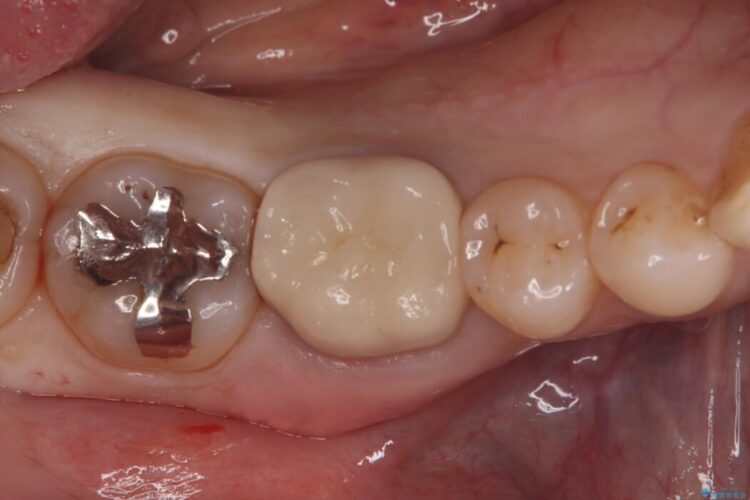

右下奥歯(7番)に違和感があるとご相談にいらっしゃった患者様です。

診査の結果、古い銀歯の隙間から新しい虫歯が広がっていました。ここは噛む力が強くかかる場所のため、このまま詰め物で治すと、部分的な詰め物では残存している自分の歯に負担が集中し、将来的に歯が割れてしまう「歯冠破折」のリスクが高い状態でした。